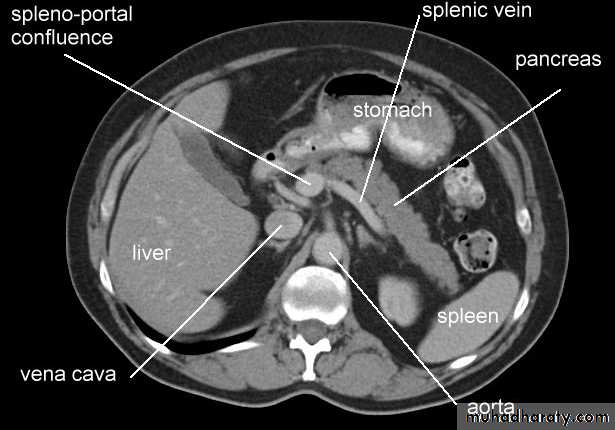

Normal pancreas in a post contrast CT